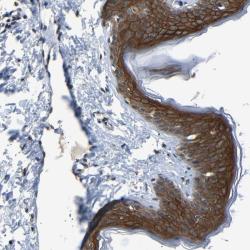

- Immunohistochemical staining of human skin shows distinct cytoplasmic and membranous positivity in epidermal cells.

- Validation comment

- Staining pattern consistent with experimental and/or bioinformatic data.